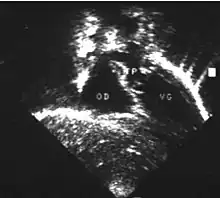

- la coupe parasternale gauche grand axe : elle montre que le vaisseau issu du ventricule gauche (le plus postérieur) se dirige anormalement vers l'arrière et se bifurque précocement. C'est donc le tronc pulmonaire et non l'aorte comme normalement ;

- les coupes sous costales qui montrent bien le trajet parallèle des gros vaisseaux et leur inversion.